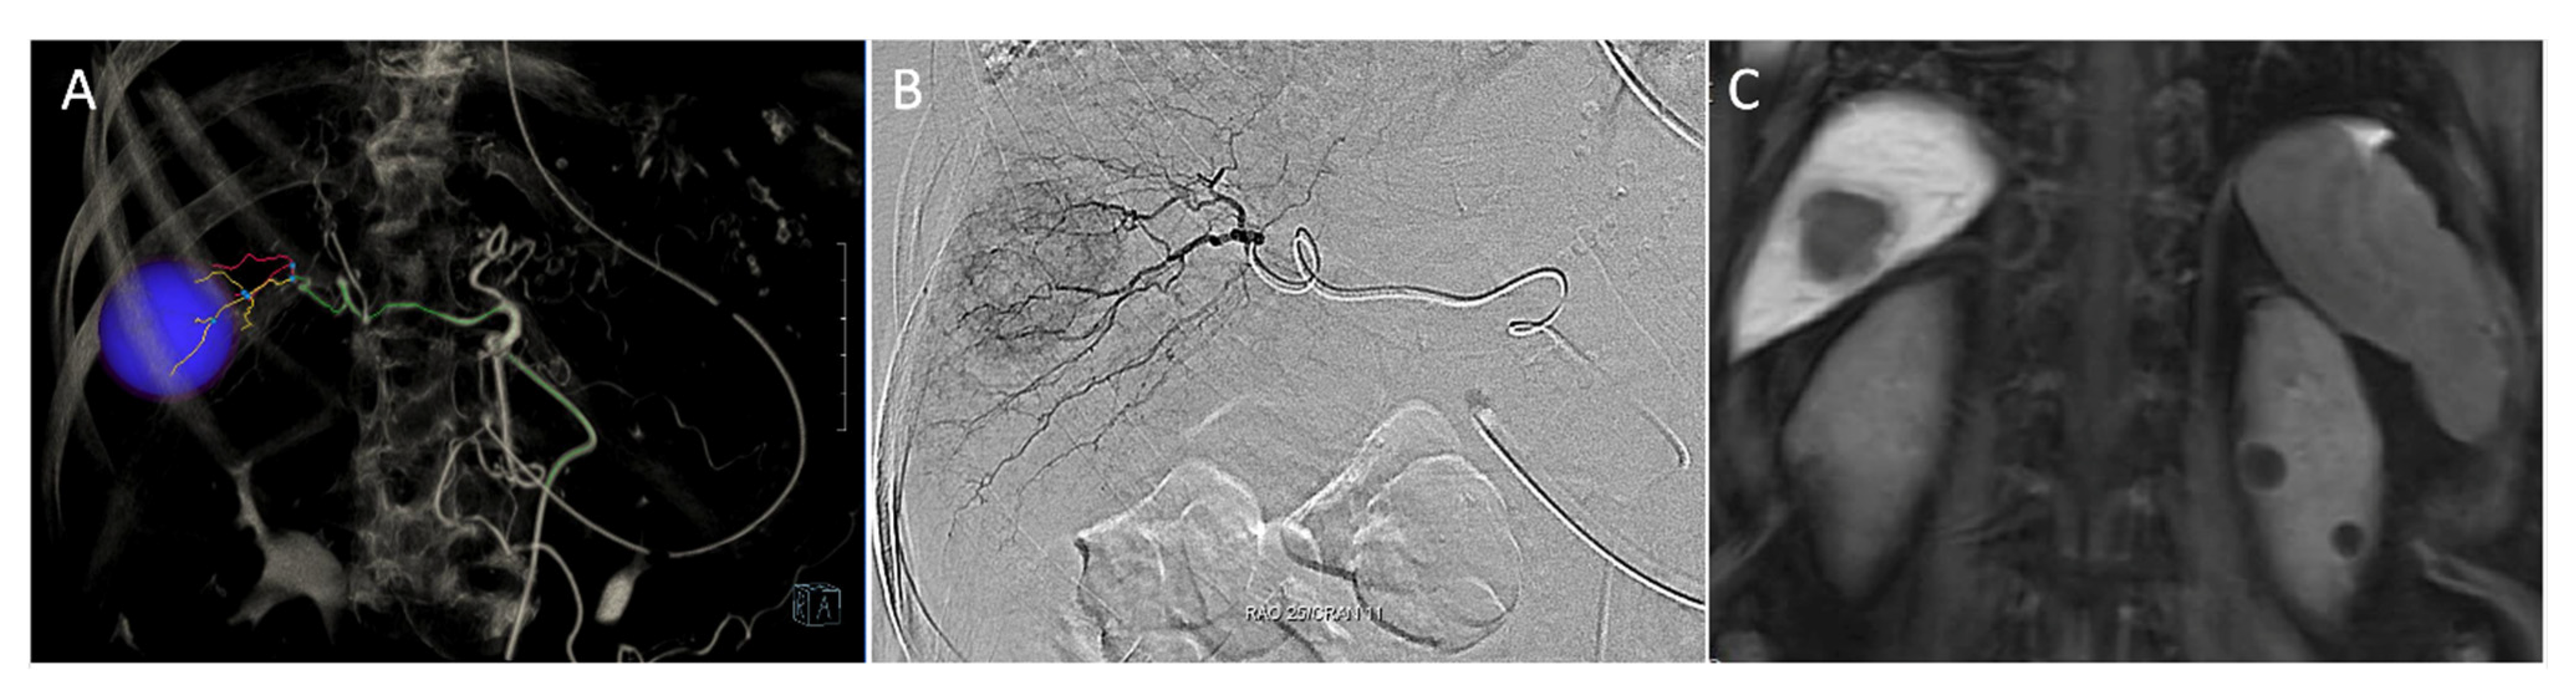

- Ueno, M.; Hayami, S.; Sonomura, T.; Tanaka, R.; Kawai, M.; Hirono, S.; Okada, K.I.; Yamaue, H. Indocyanine green fluorescence imaging techniques and interventional radiology during laparoscopic anatomical liver resection (with video). Surg. Endosc. 2018, 32, 1051–1055. [Google Scholar] [CrossRef] [PubMed]